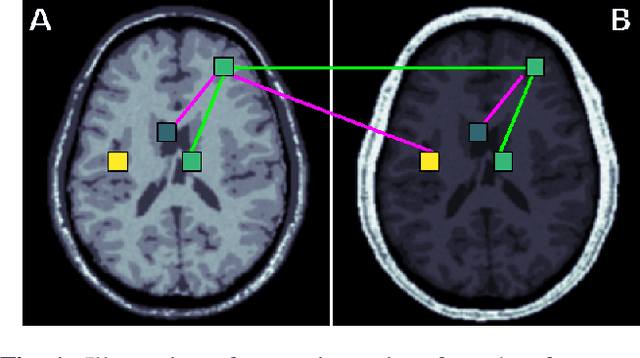

Abstract:Generalization of voxelwise classifiers is hampered by differences between MRI-scanners, e.g. different acquisition protocols and field strengths. To address this limitation, we propose a Siamese neural network (MRAI-NET) that extracts acquisition-invariant feature vectors. These can consequently be used by task-specific methods, such as voxelwise classifiers for tissue segmentation. MRAI-NET is tested on both simulated and real patient data. Experiments show that MRAI-NET outperforms voxelwise classifiers trained on the source or target scanner data when a small number of labeled samples is available.

Abstract:Voxelwise classification approaches are popular and effective methods for tissue quantification in brain magnetic resonance imaging (MRI) scans. However, generalization of these approaches is hampered by large differences between sets of MRI scans such as differences in field strength, vendor or acquisition protocols. Due to this acquisition related variation, classifiers trained on data from a specific scanner fail or under-perform when applied to data that was acquired differently. In order to address this lack of generalization, we propose a Siamese neural network (MRAI-net) to learn a representation that minimizes the between-scanner variation, while maintaining the contrast between brain tissues necessary for brain tissue quantification. The proposed MRAI-net was evaluated on both simulated and real MRI data. After learning the MR acquisition invariant representation, any supervised classification model that uses feature vectors can be applied. In this paper, we provide a proof of principle, which shows that a linear classifier applied on the MRAI representation is able to outperform supervised convolutional neural network classifiers for tissue classification when little target training data is available.